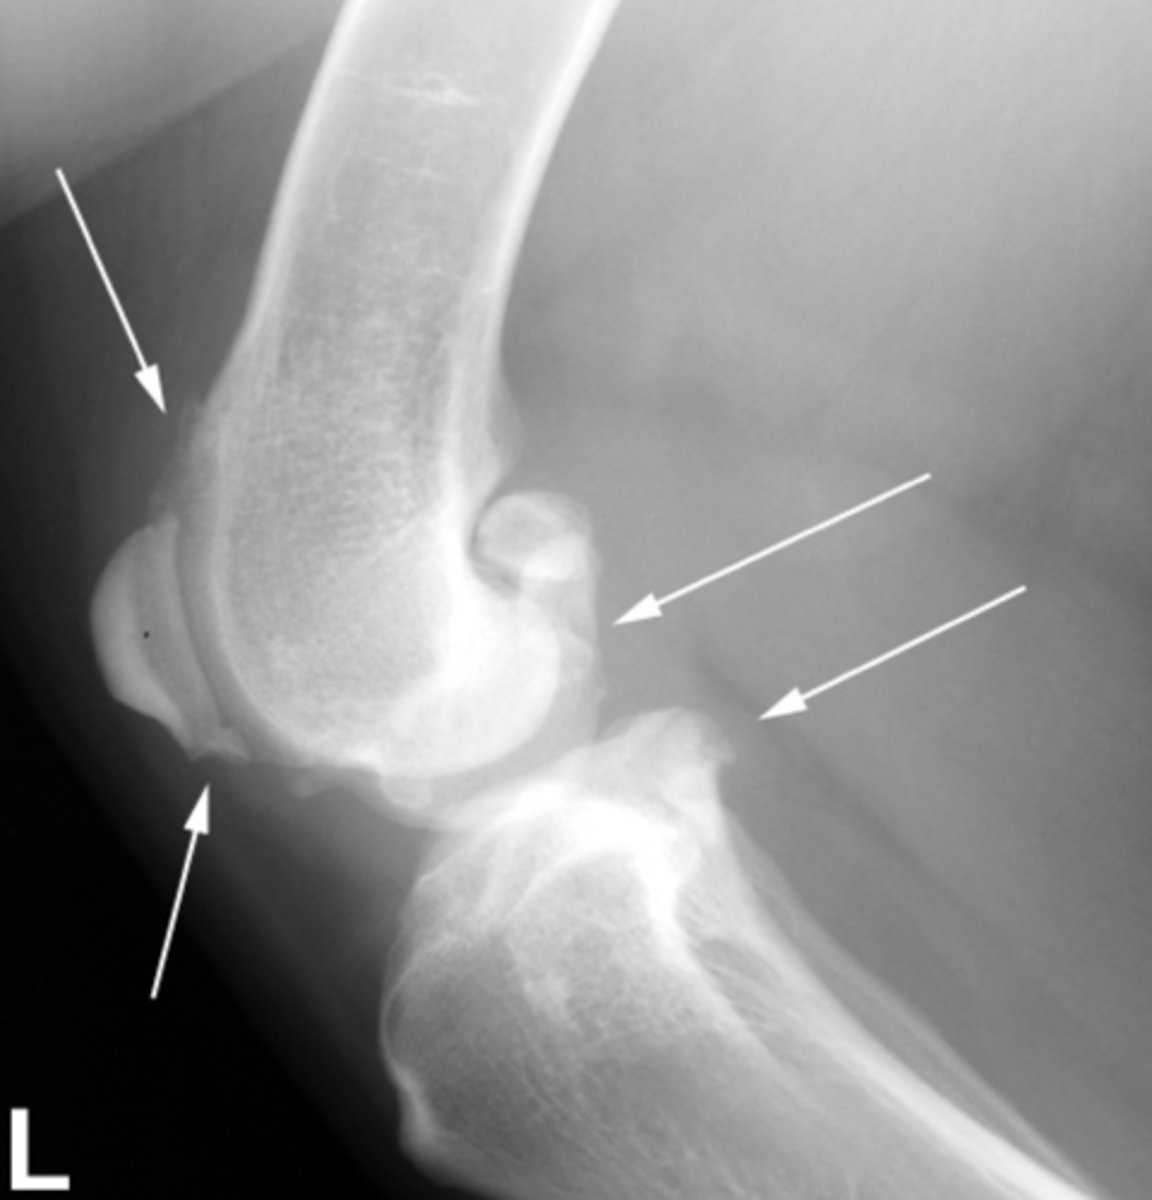

Identify the joint changes?

Monoarthrosis - Osteoarthritis - smooth regular bone less swelling